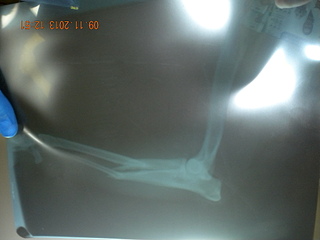

Мы с Леной (Виши) отвезли его на рентген в Бим- трещины в тазу, перелома задних лап нет. Передняя лапа сломана.

По мнению Жуйкова, требуется операция по установке титановой пластины. Стоимость операции в Биме 6-7 тысяч рублей.